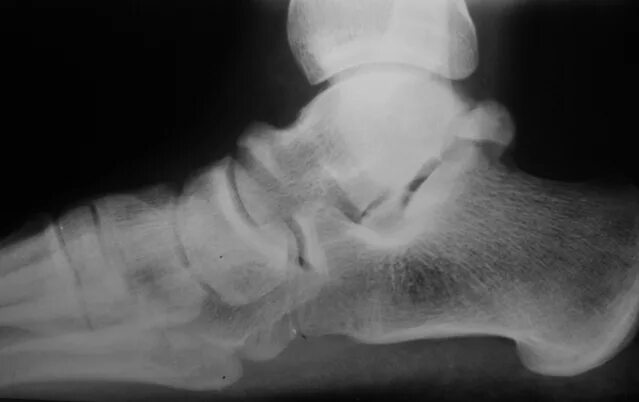

Перелом заднего